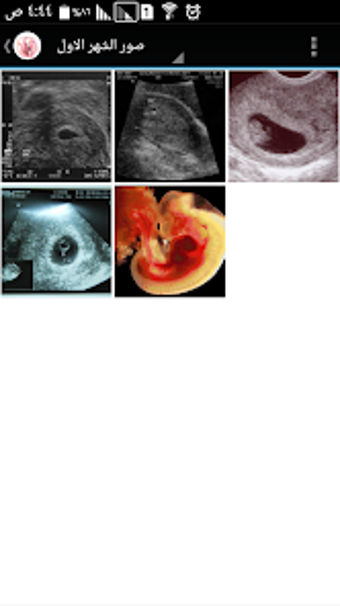

The Pregnancy and Birth Calculator App by metraqapps is a free Android utility tool app designed for expecting mothers. This app provides an extensive guide to pregnancy, including a month-by-month breakdown of fetal development, symptoms, and tips for a healthy pregnancy. The app also includes a pregnancy calculator to determine the due date and a contraction timer to help track labor.